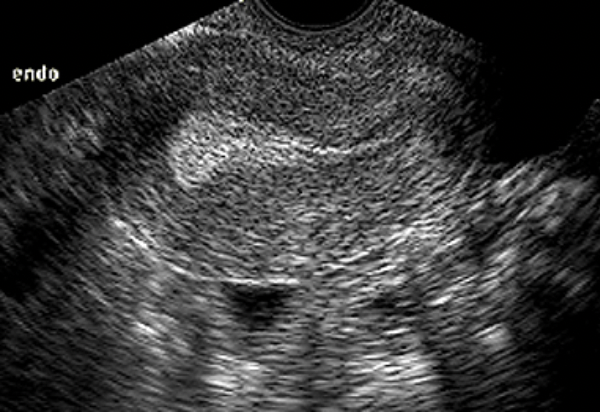

Qual diagnóstico ?

Corpo Lúteo - Cisto anexial com vascularização periférica